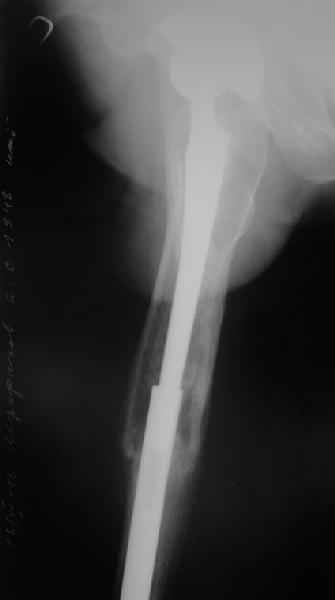

Произведено закрытое удлинение ножки эндопротеза с помощью ретроградного интрамедуллярного стержня. Продолжительность операции 3 часа. Два из них закрытое восстановление длины бедра диистрактором

таз-бедро.

А нельзя ли увидеть и профиль бедра на всем протяжении, т.е. и весь протез, и весь стержень? И фас бы с коленом.

новые снимки

Пациента удалось осмотреть недавно. Достигнутый результат сохраняется. Перелом бедра сросся. Конечность опорная и безболезненная, ходит без трости. Ножка, похоже, реинтегрировалась, как и надеялись. Снимки и фото в приложении. Комментарии приветствуются.

Надо ли что-то делать дальше, как полагаете? Убрать винты? Убрать "удлинитель ножки"? Или оставить все, как есть? Спасибо заранее.